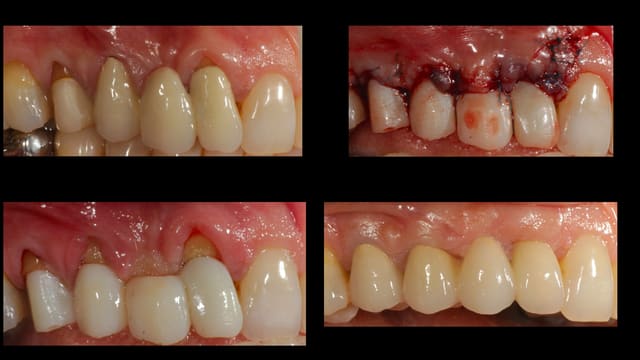

Reprise des endos, freinectomie, elongation coronaire et re-couronne.

J'avais complètement zappé ce post, je viens de revoir la patiente pour un contrôle a un an et demi post-op.

voici les images.

Pour la longueur de 'élongation coronaire j'ai essayé d'allonge au maximum les centrales tout en gardant une certaine longueur de racines pour pas trop hypothéquer l'avenir de ses dents, non ce n'est pas que du feeling mais bien sûr il faut savoir faire des compromis ;) Pour la technique j'ai juste mesuré avec une sonde paro.

Pourquoi ne pas avoir essayer de raccourcir les latérales, parce que ça voulait dire épaissir sur les latérales donc les vestibuler encore plus, mais ça m'arrive d'en faire je te joins ou il me semble que c'était plus indiqué.

Non je ne savais pas à l'avance que j'obtiendrai un résultat pareil, pour répondre à ta question on avait fait un wax a l'avance, en fait même deux pour ce cas là j'avais faire une première chirurgie d'élongation coronaire, mais comme je n'étais pas satisfait j'en ai fait une deuxième.

Effectivement sur ce cas on s'éloigne de la composition dentaire idéal décrite dans la littérature mais si tu reprends les articles de Vince Kokich sur la perception du sourire par les dentistes, orthodentistes et patients, tu verras que le plus important dans un sourire harmonieux c'est la verticalité de la ligne inter-incisive et la symétrie des centrales, donc là l'objectif c'est de redonner aux centrales une taille (entre 10 et 11 mm ) et une proportion normale ( autour des 80 % de rapport L/l )et d'essayer d'harmoniser le tout.